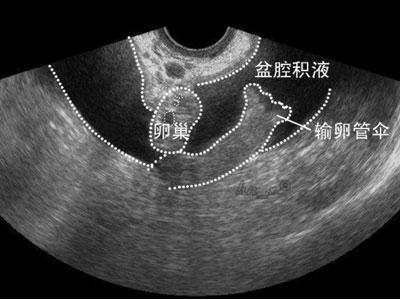

在开始有B超有,越来越多的人发现盆腔积液了。只能说以前你没发现你也是有积液的,只是现在B超做的多了,就发现的多了。

上面这张图片其实有点危言耸听了,盆腔积液也有非病理性的。

比如排卵的时候,卵泡液流入盆腔,那么B超看来就是盆腔积液,而这是非病理性的。

还有,如果近期做过宫腔镜、输卵管通液之类的手术,也难免会有积液,毕竟手术中液体流入盆腔集聚,B超看来也是盆腔积液。